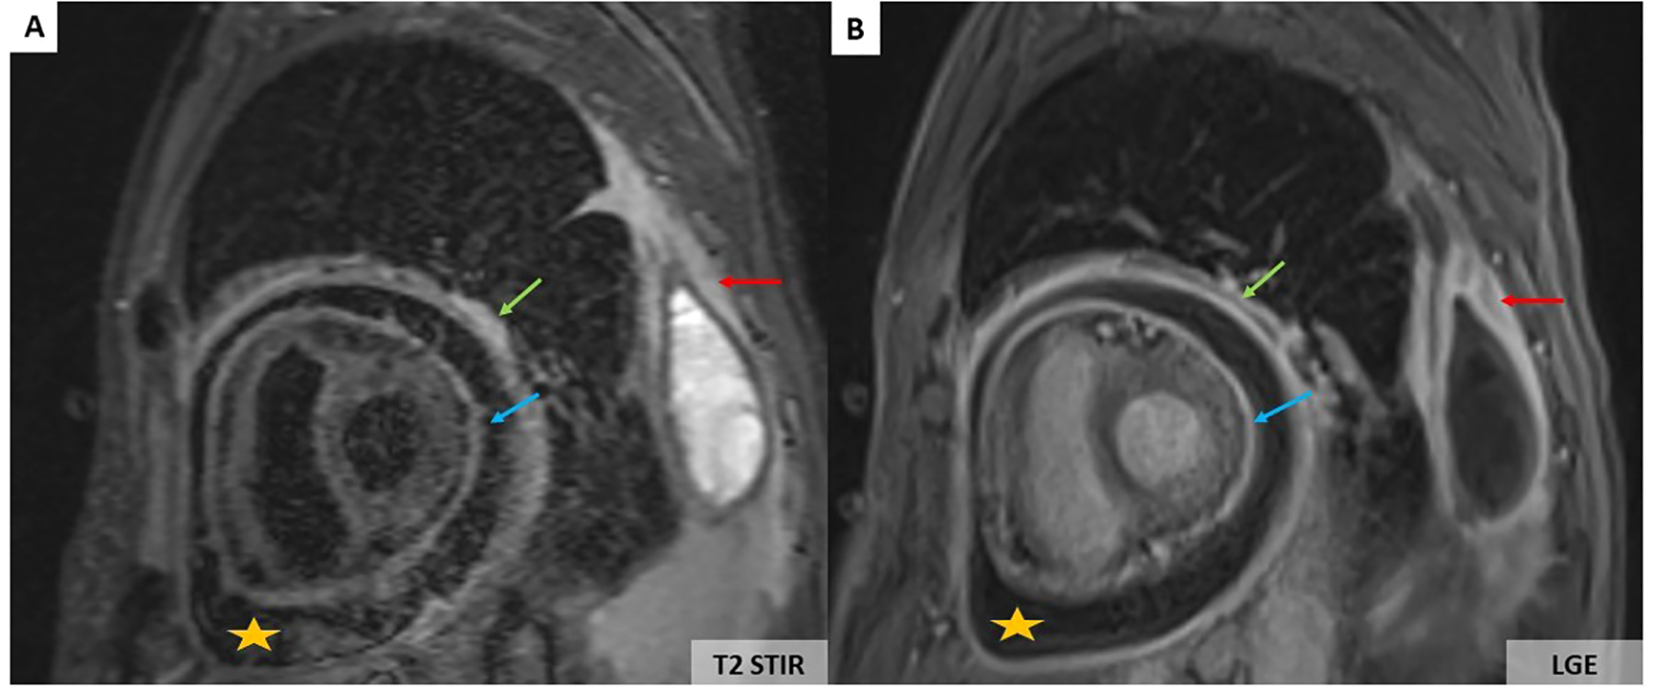

However, a progressive dyspnoea appeared a month later (November 2024) leading to performing a transthoracic echocardiography which revealed a moderate pericardial effusion without echocardiographic signs of cardiac tamponade. The troponin level was normal, and C-reactive protein values increased up to 12 mg/L. The patient received a 2-week course of non-steroidal anti-inflammatory drugs in combination with acetaminophen. His clinical status did not improve, and the C-reactive protein level further increased to 110 mg/L. Cardiovascular magnetic resonance (CMR) imaging showed large pericardial effusion associated with thickened pericardium (Figures 2A, B).

Figure 2

CMR showing large pericardial effusion (orange stars) associated with thickening of the pericardium (A, B). On the T2-weighted short-tau inversion recovery (STIR) sequence, there is an increase in signal of the parietal (green arrows) and visceral pericardium (blue arrows) suggesting recent pericardial inflammation (A). Pericardial hyperenhancement of the thickened parietal and visceral pericardium secondary to pericardial inflammation associated with left pleural thickening (red arrows) on the late gadolinium enhancement sequence (B).

Pericardium, myocardium, and coronary arteries lesions are observed in up to 40%–70% of ECD patients (10). Clinical presentations may be severe with worse prognosis. Arrhythmias, myocardial ischaemia, valvular dysfunction, and heart failure are more common in older patients (10). Cardiac MRI performed at baseline can identify cardiac involvement and evaluate the extent of ECD (10). The pericardium may be thickened with effusion that can cause cardiac tamponade (Figures 2A, B). However, massive pericardial effusions are rare (10). Myocardial infiltration usually involves the right atrium and right atrioventricular groove. Myocardial involvement is best seen on MRI as T1W hypointense focal lesions with post-contrast enhancement. Infiltration of coronary arteries is reported in 23% of patients, most commonly the right coronary artery, and can lead to ischemic cardiomyopathy (10).